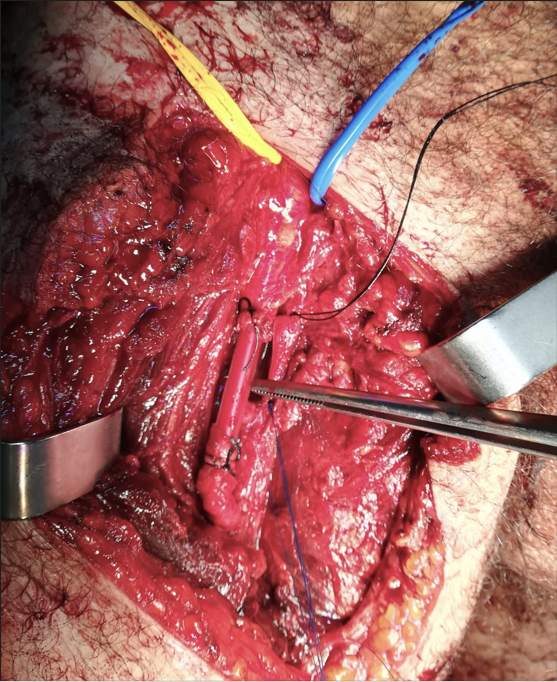

In the operative room a horizontal groin incision was performed with dissection to the right femoral artery and vein to allow vascular clamp (Figure 1). After proximal control was achieved, the exploration of the thigh wound reveal a complete superficial femoral artery and vein transection. Femoral vein ligation and artery shunt was performed with a silicone tube of an esophageal stethoscope. The shunt was inserted into the proximal and distal vessel and secured with thick silk tie (Figure 2). Hand-held Doppler evaluation of flow confirmed the patency two hours after damage control surgery.

Figure 2 Superficial femoral artery shunt.

In the immediate post-operative period, the patient was transferred to a specialized center where, only four hours after the injury, the final revascularization was accomplished by interposition of the contralateral great saphenous vein in reverse. Post-operatively, Doppler evaluation confirm shunt patency and distal flow.